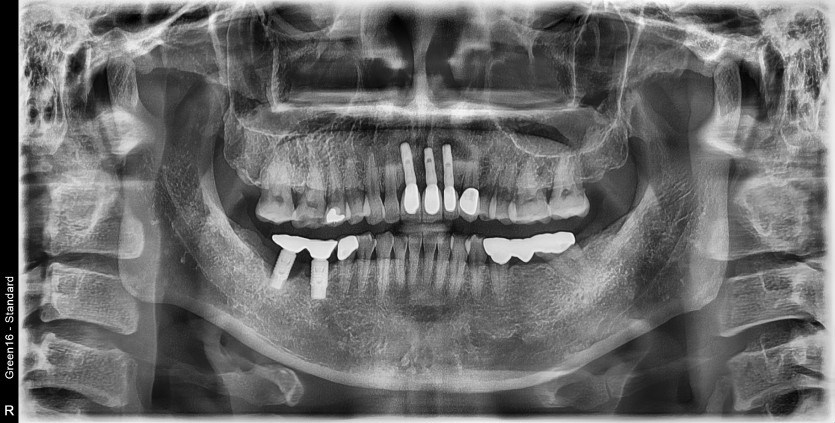

#46,47 임플란트 재수술